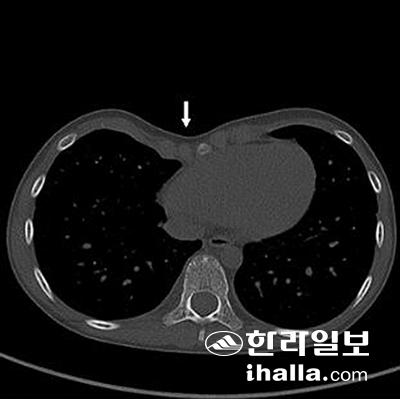

제주대학교병원을 방문한 환아 A의 흉부CT에서 움푹 패인 흉곽(화살표)을 확인할 수 있다.